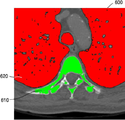

도 11 및 도 12는 본 발명의 일 실시 예에 따라 의료영상에서 영역을 분리한 결과를 도시한 도면이다.BRIEF DESCRIPTION OF THE DRAWINGS FIG. 1 is a diagram showing a simple example of a system for photographing and processing a three-dimensional human body image according to the present invention;

분리부(240)는 절단링크를 따라 링크를 절단하였을 때 복셀노드가 두 영역으로 분리될 때까지 최단경로를 검색하고 절단링크를 파악하는 과정을 반복수행한다. 간단한 예를 통한 복셀링크의 분리과정은 도 9에 도시되어 있다. 분리부(240)에 의해 의료영상으로부터 분리한 생체 기관의 일 예가 도 11 및 도 12에 도시되어 있다. When the link is cut along the cut link, the